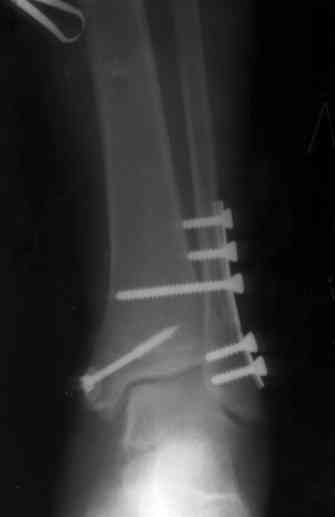

Re: Перелом обеих лодыжек и з/края б/б кости с выв

После проведенной дискуссии пришел к выводу, что трансартикулярная диафиксация не совсем приемлима с учетом современных методик остеосинтеза. Кроме того, вычитал, что хрящ разрушается на расстоянии до 0,5 см от места проведения спицы.

Пока я был в интернатуре, предпочитали осуществлять стабильный остеосинтез с ранней функцией. См. приложения и полнотекстный вариант

статьи.